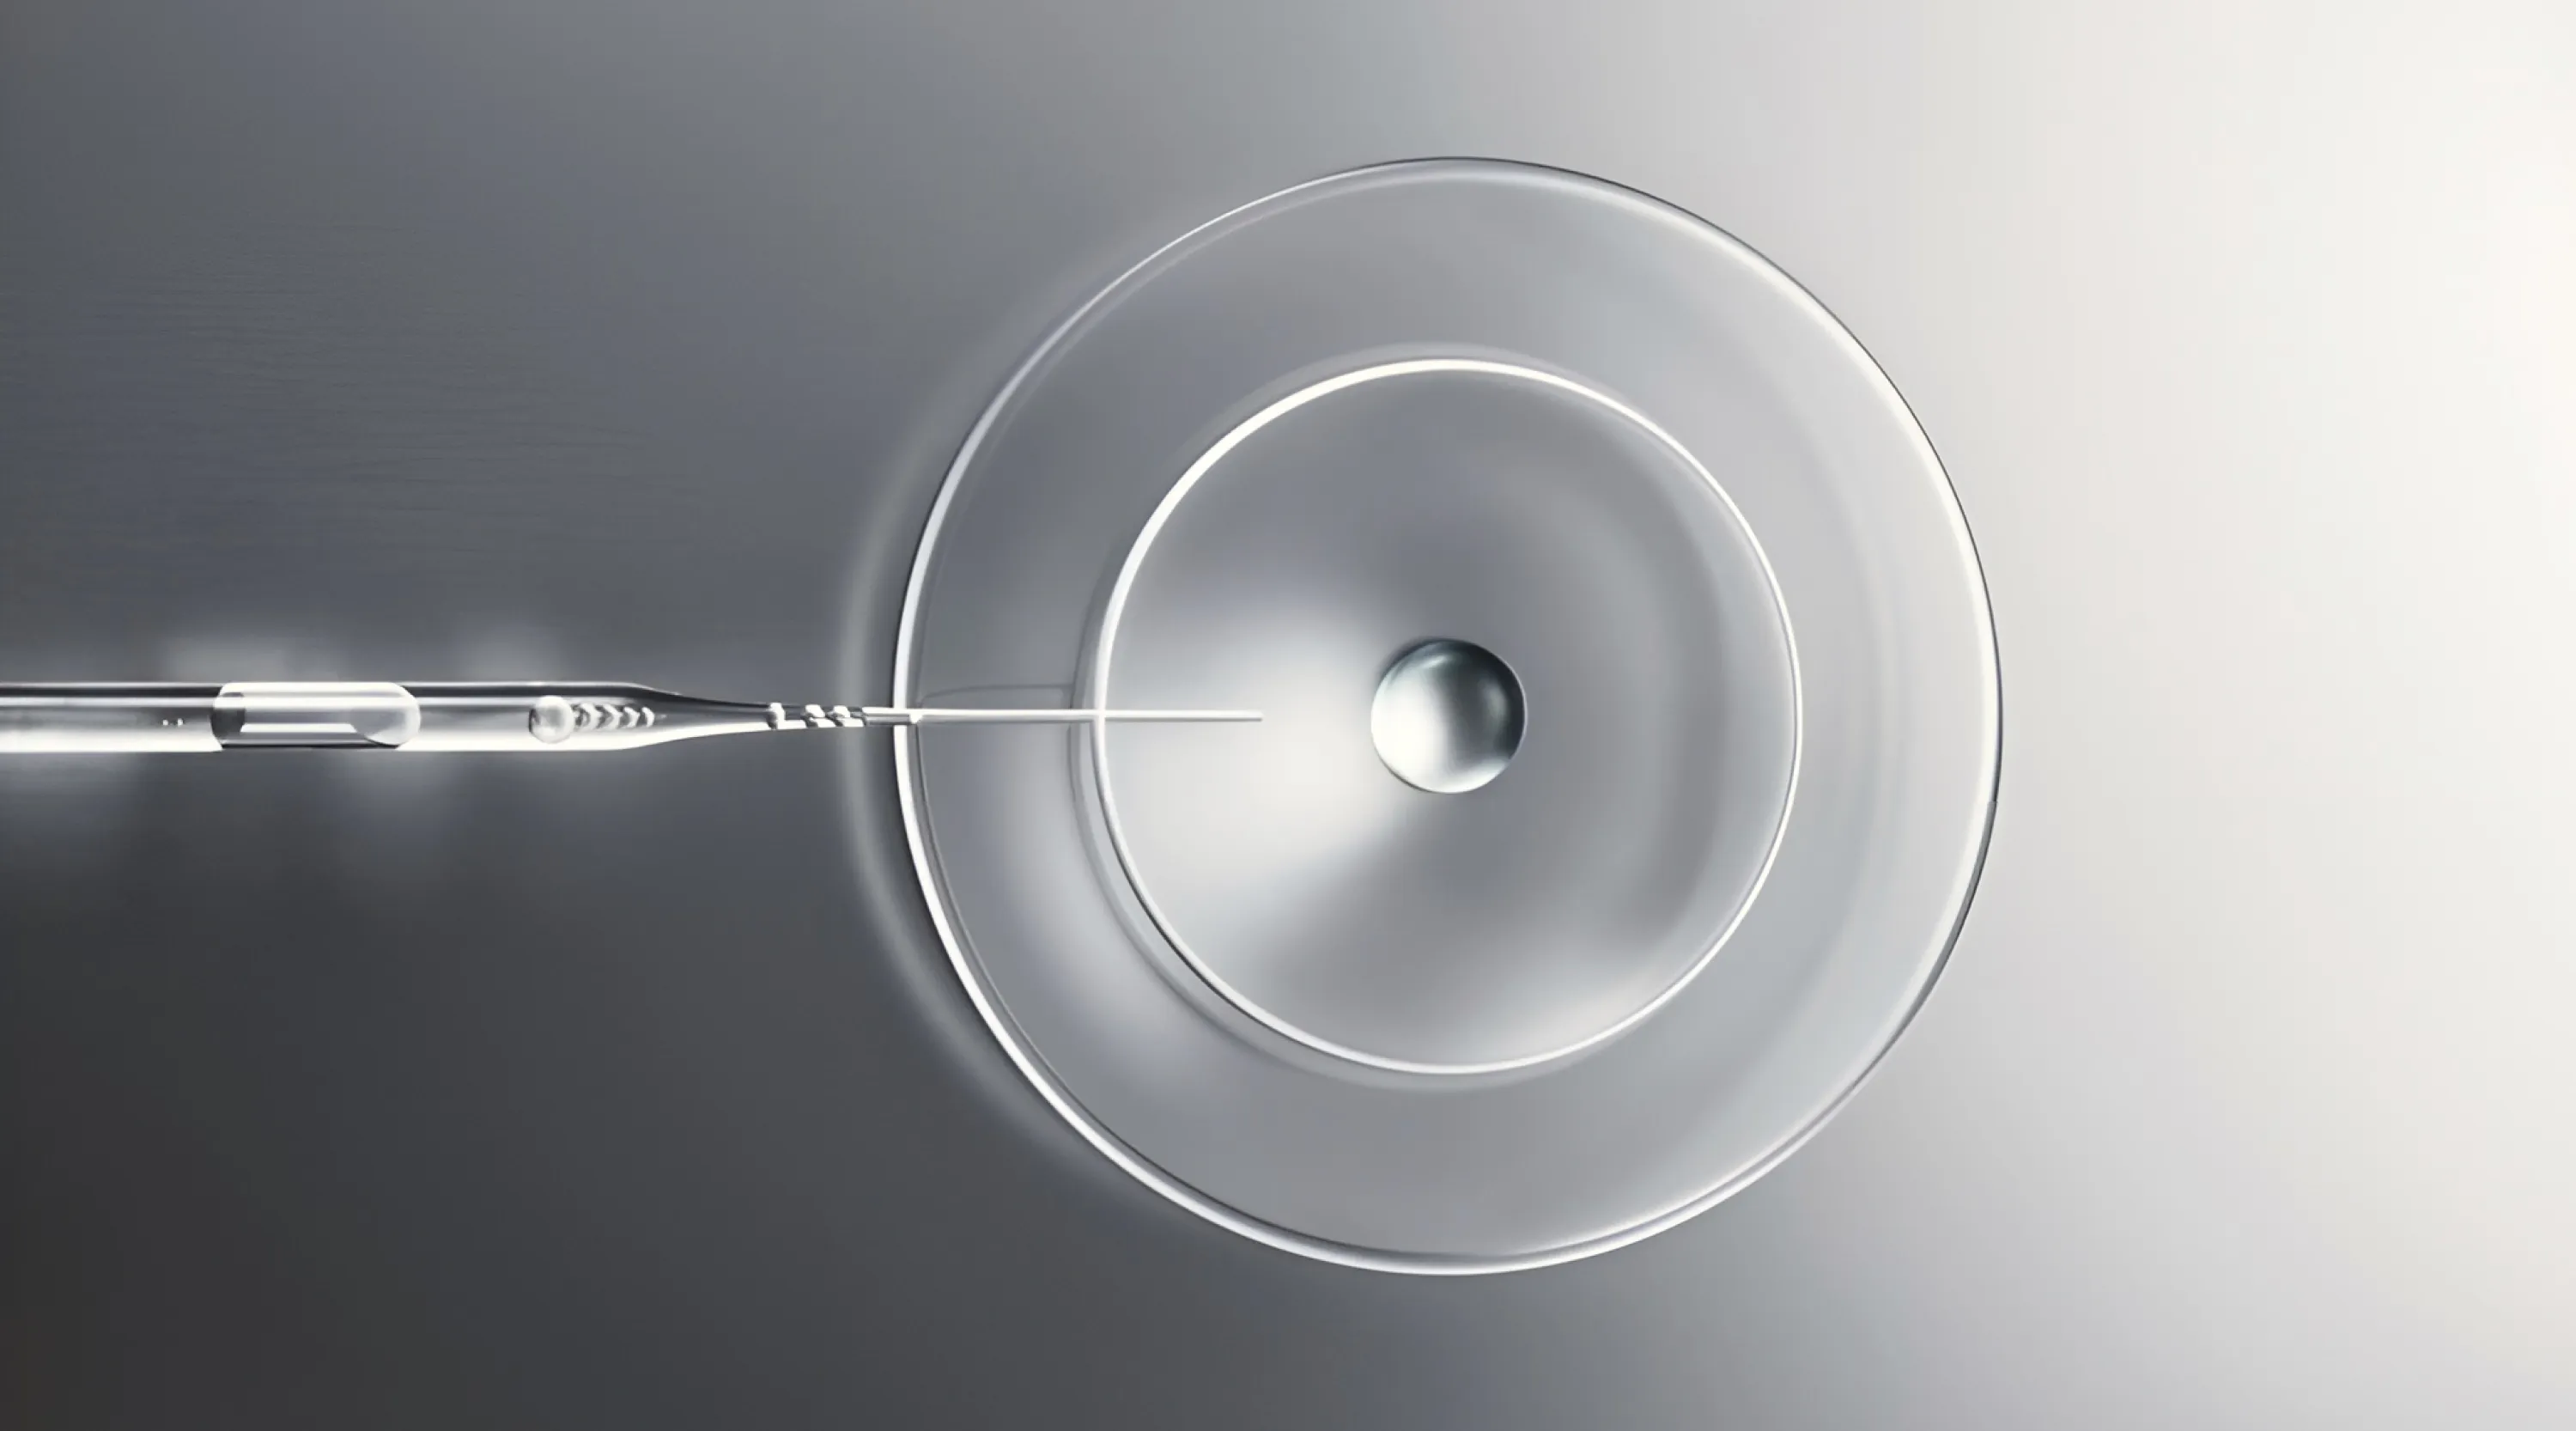

▪️ Получаем максимум из плазмы пациента для запуска регенеративной функции с помощью факторов роста.

▪️ PRGF в трихологии: обоснование и клиническая эффективность.

▪️ Что представляет из себя регенеративная лаборатория Ycellbio?

▪️ Уникальные особенности технологии и легкость применения умной пробирки YCELLBIO.